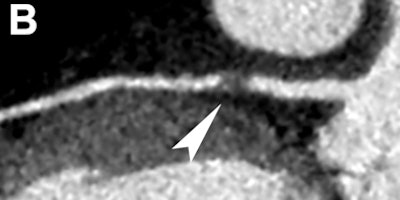

| Images are of a 42-year-old man with atypical chest pain and no significant ECG or troponin alterations. Clinical assessment was in favor of mild pericarditis. CT shows in 3D volume rendering (A) and curved multiplanar reformats (B) the presence of an obstructive atherosclerotic plaque at the proximal left anterior descending coronary artery (arrowhead). Image courtesy of Dr. Filippo Cademartiri, PhD. |